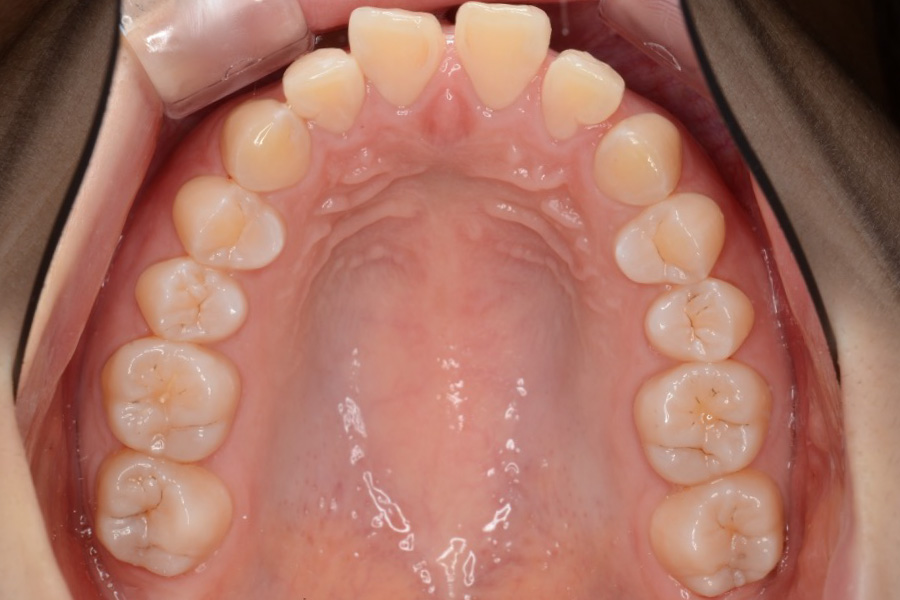

【20代女性】

歯の突出感、スペースを

インビザライン矯正で治療したケース

治療前

| 主訴 | 歯の突出感、スペースが気になる |

| 期間 | 2年半 |

| 費用 | 220,000円〜660,000円 (デンタルローン 3,100円〜6,600円/月) |

| 治療内容 | インビザライン矯正 非抜歯 |

| 治療に伴うリスク | 矯正終了後は、リテーナーを指示通りに使用し、歯の後戻りを防ぐ必要があります。 |